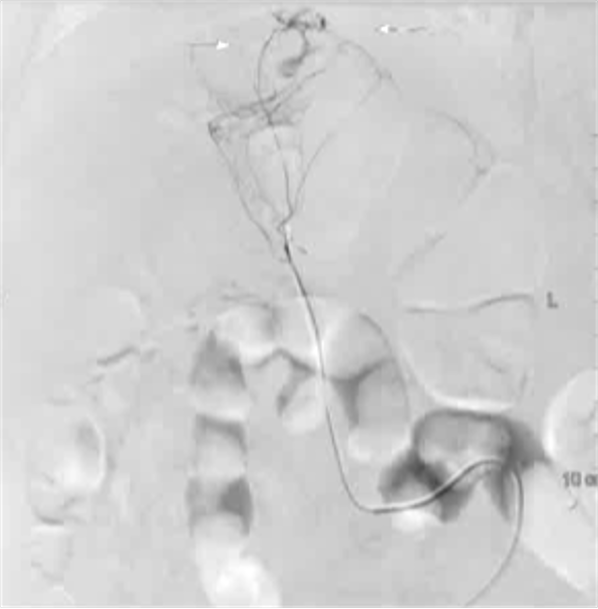

病例1 70/40 mmHg

病例1 20μg Arterenol (去甲肾上腺素) 155/85mmHg

|

激发下 |

栓塞后 |